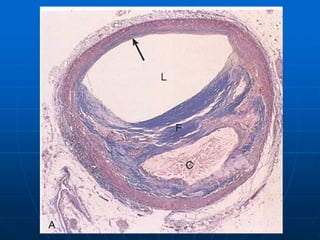

Normal koroner damar kesiti

ATEROSKLEROZ